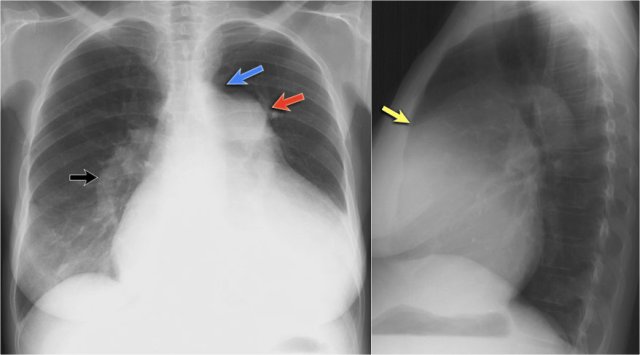

Silhouette sign (3)

Here a consolidation which is located in the left lower lobe (yellow arrow).

Notice that there is a normal silhouette of the left heart border (blue arrow).

The absence of a silhouette sign tells us that the pathology is located in the left lower lobe and not in the lingula.

Silhouette sign (4)

On this lateral film there is too much density over the lower part of the spine.

First study the lateral film and decide on which side the pathology is located.

By only looking at the interfaces of the left and right diaphragm on the lateral film, it is possible to tell on which side the pathology is located.

In this case we cannot follow the contour of the right diaphragm all the way to posterior, which indicates that there is something of water-density in the right lower lobe.

Continue with the PA-film of the same patient...

On the PA-film there is a normal silhouette of the right heart border, so the pathology is not in the anterior part of the chest, which we already had decided by studying the lateral view.

Question:

Why do we still see the silhouette of the right diaphragm on the PA-film?

Answer:

What we see is actually the highest point of the right diaphragm, which is anterior to the pneumonia in the right lower lobe.

The pneumonia does not border the highest point of the right diaphragm and there will be no silhouette sign.